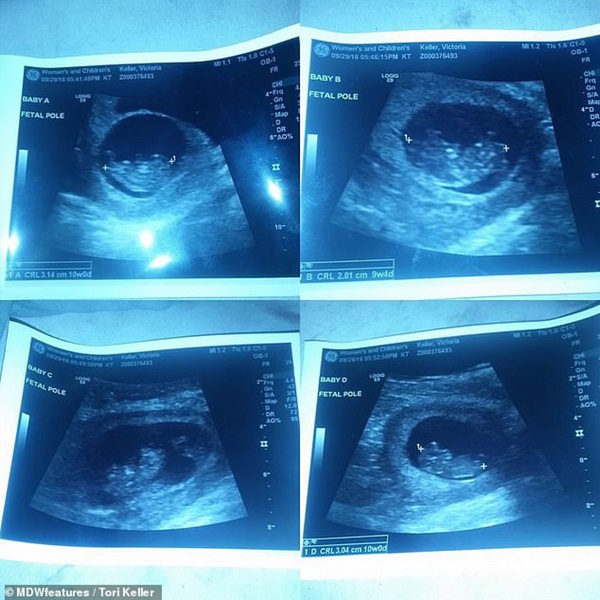

Điều bất ngờ đó là cô Tori mang thai 4 đứa con khiến cặp vợ chồng rất ngạc nhiên. Thậm chí cô Tori còn nghĩ rằng bác sĩ nói đùa cho đến khi tận mắt nhìn thấy ảnh siêu âm. Các bác sĩ cũng cho biết em bé A trong bụng có túi ối và nhau thai riêng, trong khi 3 bé B, C, D phải chia sẻ cùng nhau một nhau thai và túi ối. Chính điều này đã mang đến những rủi ro khi mang thai.

Hình ảnh siêu âm của 4 bé trong bụng.